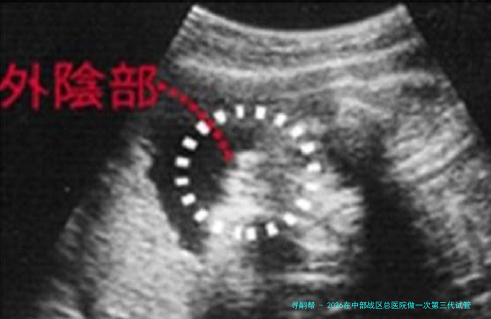

胚胎活检与筛查:对发育至囊胚期的胚胎进行活检,样品送检验进行遗传课程分数析。

胚胎移植与验孕:根据筛查结果,选择健康的胚胎进行移植,手术之后进行黄体支持并在规按时间验孕。